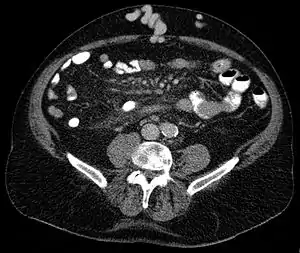

| Axial CT showing portosystemic collateral circulation via the umbilical vein: caput medusae in سیروز | |